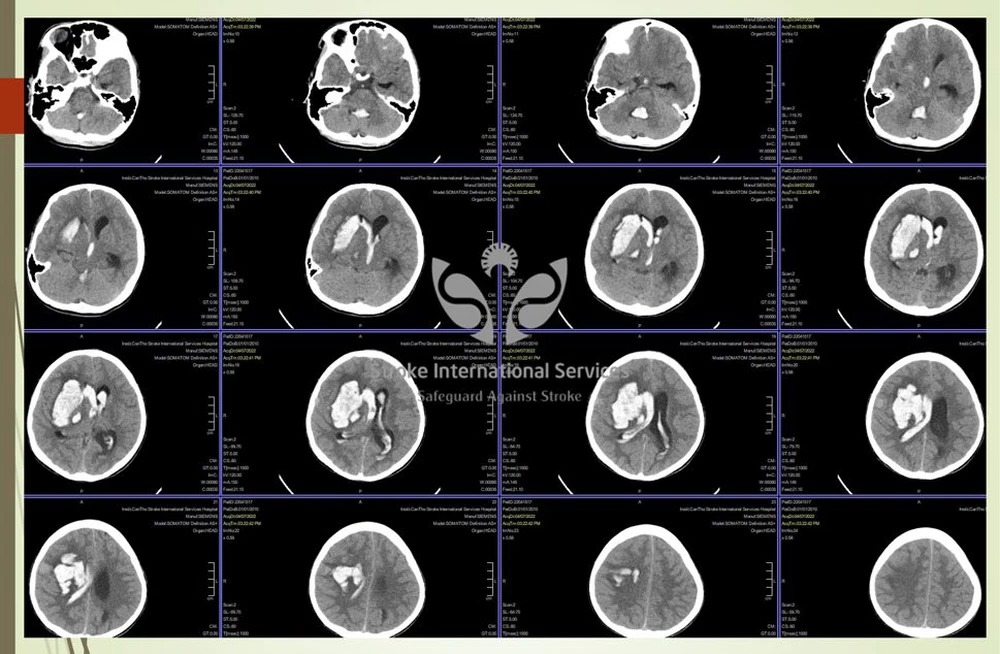

Thông tin trên Tổ Quốc, bệnh nhi vào cấp cứu tối 7/4 với biểu hiện đau đầu dữ dội kèm theo nôn ói. Khi vào viện bác sĩ đã nghi ngờ xuất huyết não do vỡ phình mạch máu não.

Trong y khoa, những túi phình mạch máu não được ví như bom nổ chậm, có thể vỡ gây ra cơn đột quỵ xuất huyết não bất cứ lúc nào.

Với các trường hợp chảy máu não, việc điều trị khó là tuỳ vào lượng máu chảy, vị trí xuất huyết, tình trạng lâm sàng lúc nhập viện có còn cơ hội để cứu chữa hay không. Cấp cứu các trường hợp này thời gian vẫn là yếu tố vô cùng quan trọng.

Khi xảy ra đột quỵ ở trẻ em, thì ngày nay sẽ điều trị theo phương pháp can thiệp nội mạch DSA, ít xâm lấn, đặc biệt là điều trị được những vùng não sâu mà phẫu thuật không mổ tới. Ngoài ra, sau can thiệp trẻ nhỏ bảo tồn được phần lớn chức năng, không để lại bất kỳ vết sẹo nào.